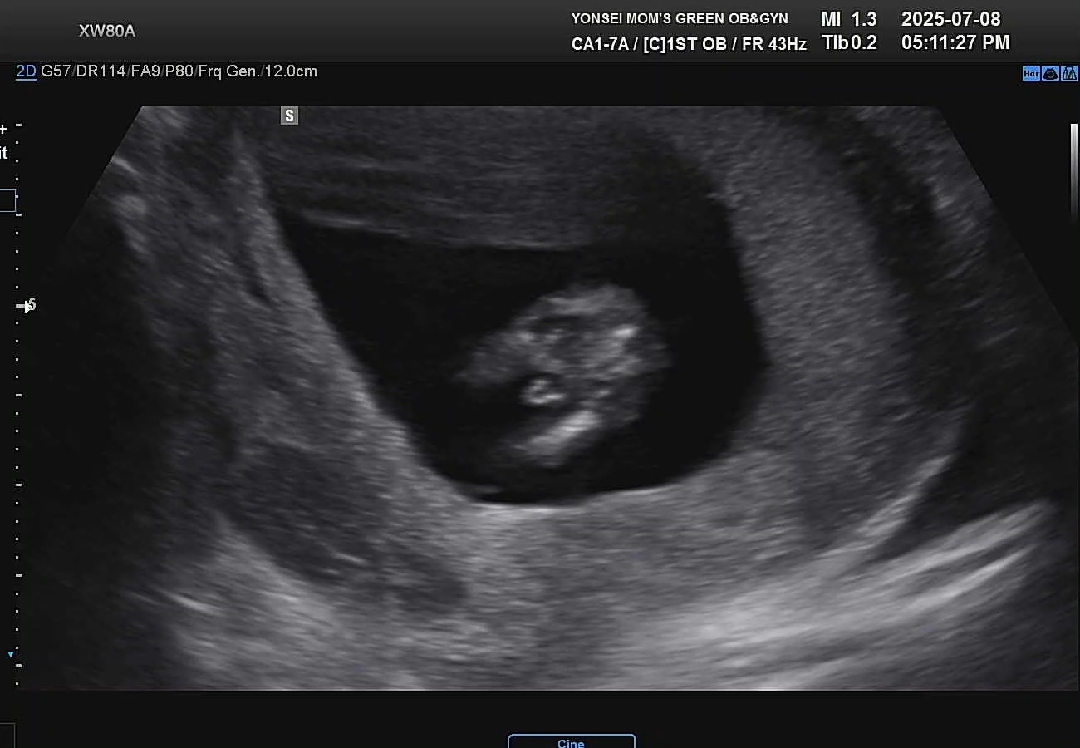

13주2일 다리사이!

성별 빨리 알고싶어서 니프티까지 했었는데.. 한주만 더 버틸껄 그랬나봐요ㅋㅋ 존재감 뿜뿜🌶 이렇게 빠르게 알게될지 몰랐어요😂